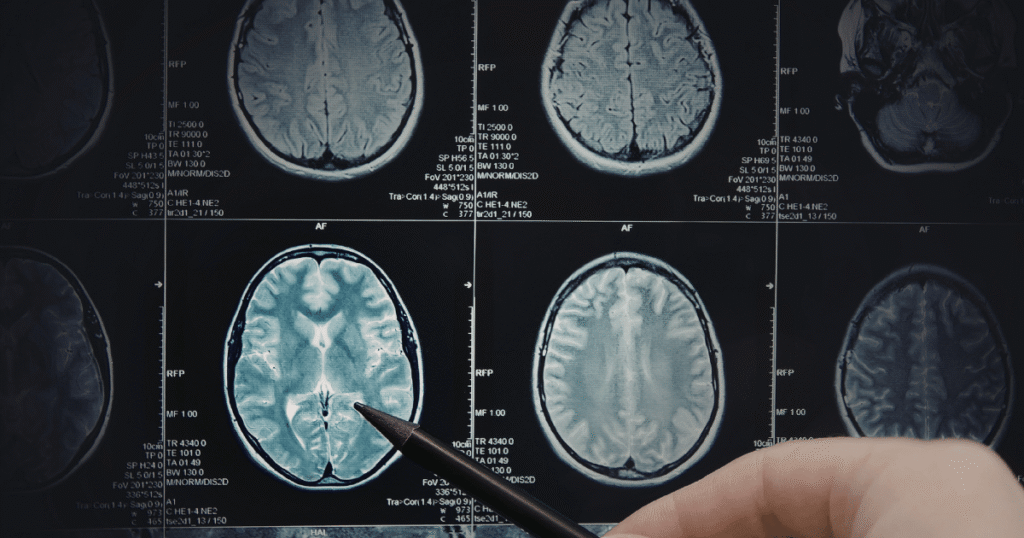

Quando o paciente entra na emergência, o exame padrão-ouro inicial é a Tomografia Computadorizada (TC) de Crânio.

Dica de Prova: Muitos alunos acham que a TC serve para “ver o AVC”. Na verdade, nos primeiros minutos do AVC Isquêmico, a TC pode vir normal! O principal objetivo da TC inicial é excluir sangue (AVCh). Se não tem sangue e o paciente tem sintomas, tratamos como isquêmico para poder entrar com a medicação fibrinolítica.

Posteriormente, a Ressonância Magnética (RM) é usada para ver a extensão exata da lesão tecidual e planejar a reabilitação.